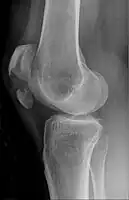

A fracture of the patella seen on a lateral view